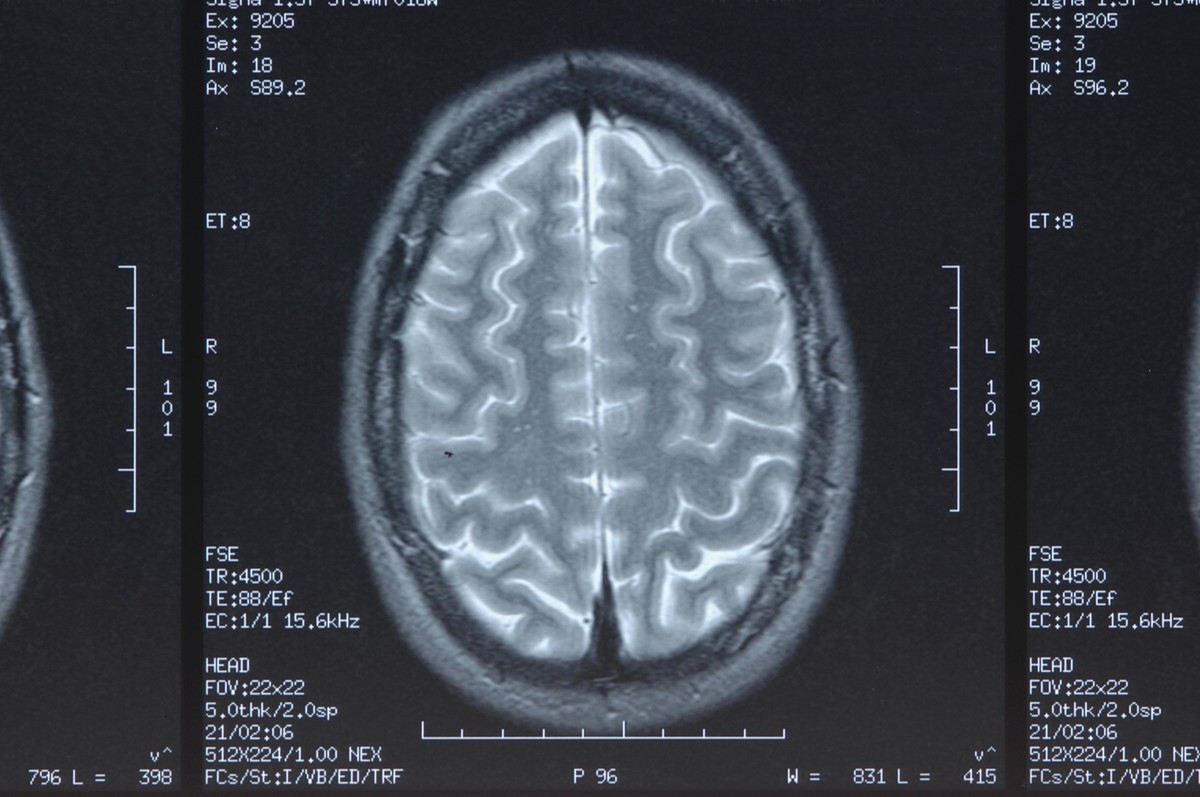

O DTM (dimetiltriptamina), um composto natural encontrado em plantas e até em mamíferos, é bastante conhecido por seus efeitos alucinógenos. Mas, agora, pesquisadores descobriram que ele pode reduzir drasticamente os danos cerebrais causados pelo acidente vascular cerebral (AVC).

Estudo do Instituto de Biofísica HUN-REN Szeged e do Centro Cardíaco e Vascular da Universidade Semmelweis, ambos da Hungria, constatou que a molécula psicoativa restaurou a barreira hematoencefálica e reduziu a inflamação em animais e células, uma indicação de que pode complementar os tratamentos existentes para AVC.

Em experimentos com animais e modelos de cultura de células, os autores demonstraram que o tratamento com DMT restaurou a estrutura e a função da barreira hematoencefálica danificada e melhorou a função das células da astroglia, que tem pepel crucial para a saúde e funcionamento do cérebro e da espinal medula.

Além disso, inibiu a produção de citocinas inflamatórias nas células endoteliais cerebrais e nas células imunes periféricas e reduziu a ativação das células da microglia cerebral por meio dos receptores Sigma-1.

“As opções terapêuticas atualmente disponíveis para o AVC são muito limitadas. A dupla ação do DMT, protegendo a barreira hematoencefálica e reduzindo a inflamação cerebral, oferece uma abordagem nova e complexa que pode complementar os tratamentos existentes”, afirmou a coautora Judit Vigh.